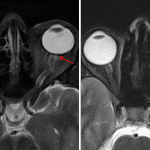

- Mild tortuosity of the bilateral intraorbital optic nerves with mild flattening along the posterior sclera bilaterally

- Idiopathic intracranial hypertension (IIH)

Constellation of findings including bilateral posterior scleral flattening, tortuous intraorbital optic nerves, empty expanded sella, bilateral distal transverse sinus stenosis, and low-lying cerebellar tonsils is typical for idiopathic intracranial hypertension (IIH). Recommend correlation with CSF pressure analysis.